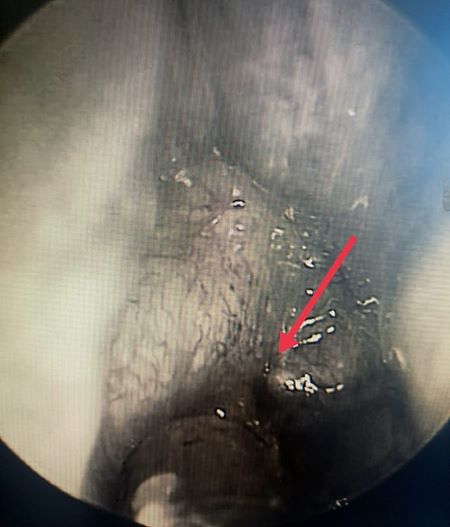

Проведена эндоскопия полости носа гибким эндоскопом: в левую половину носа эндоскоп проходит до носоглотки без препятствий, справа - большое количество слизи.

После санации правой половины носа визуализируется частичная мембранозная атрезия хоаны.